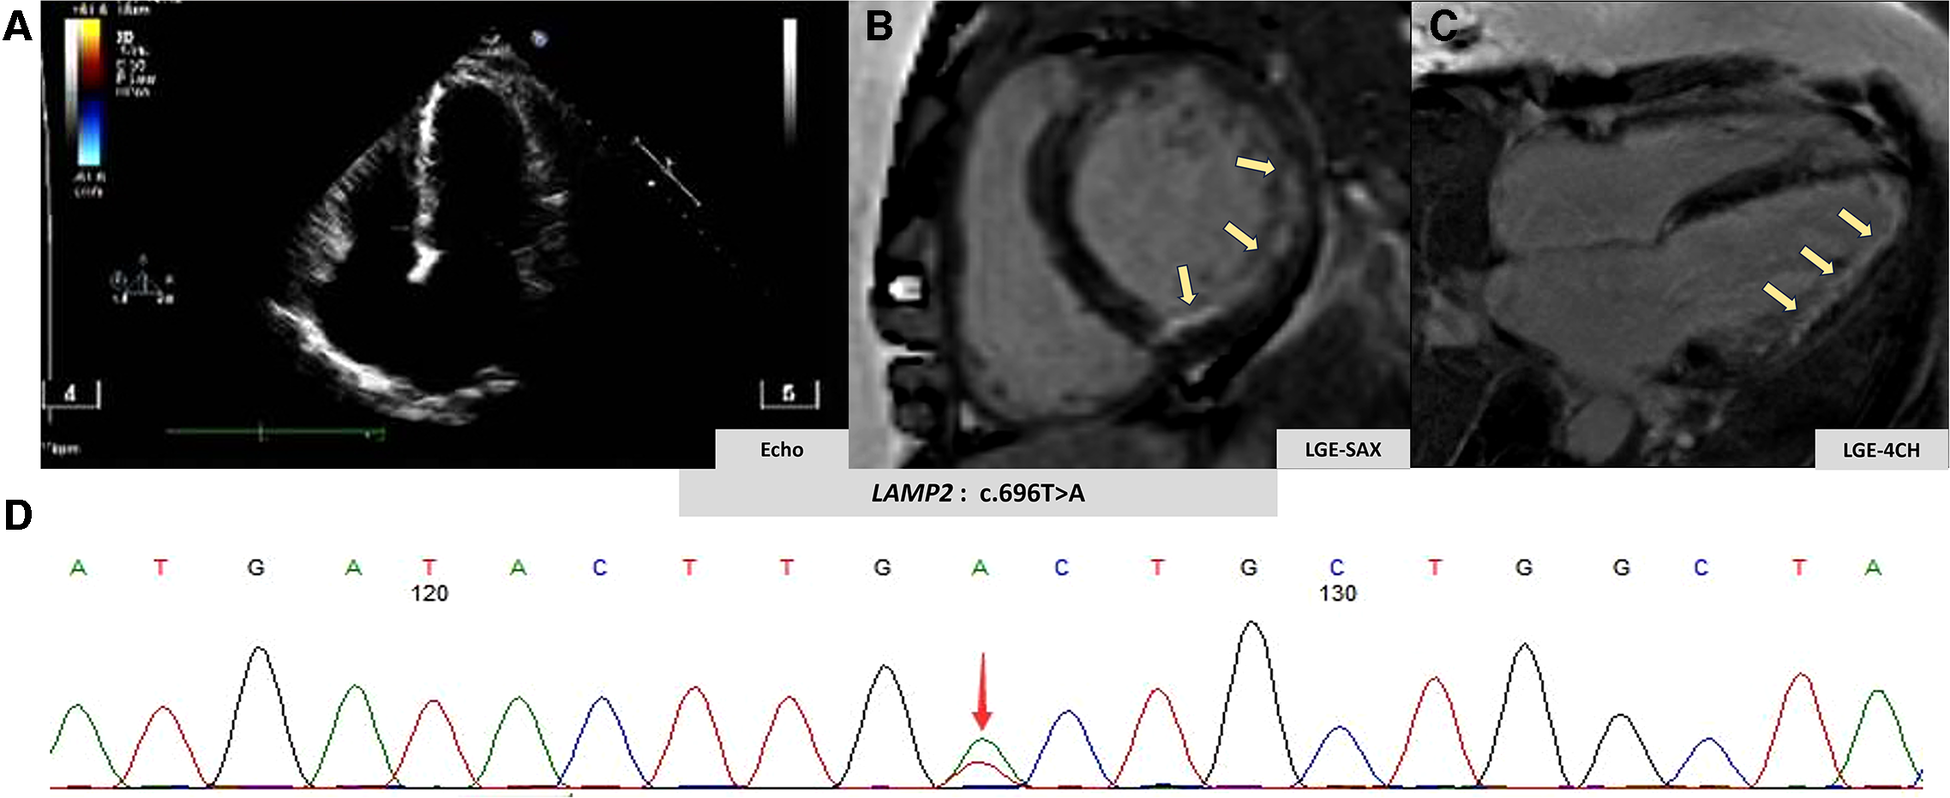

A 51-year-old woman was admitted to our emergency department due to hemodynamically stable ventricular tachycardia (VT). Her family history was unremarkable for cardiovascular disease, sudden death, or other inherited disorders. Apart from a long history of arrhythmias, she had no special medical or psychosocial record. The patient experienced recurrent paroxysmal palpitations since she was 15 years old. In her 30s, she was diagnosed with Wolff–Parkinson–White (WPW) syndrome (Figure 1A) with paroxysmal supraventricular tachycardia, for which she received her first radiofrequency catheter ablation (RFCA). Echocardiography at that time showed a normal heart, while cardiac troponin levels were not tested. Three years ago, she was admitted with paroxysmal atrial flutter (Figure 1B), during which echocardiography revealed an enlargement of the left atrium (45 mm) but normal left ventricular wall thickness (10 mm), chamber size (51 mm), and ejection fraction (EF) (72%). She was discharged after the RFCA for atrial fibrillation (AF) with a normal troponin-T level. This was her third hospitalization for palpitations. Upon admission, ventricular tachycardia (Figure 1C) was recorded, which was electrically converted to sinus rhythm with a complete left bundle branch block (Figure 1D). Despite no heart murmurs or abnormalities of other systems found in physical examination, a slightly elevated N-terminal pro-B-type natriuretic peptide (568 pg/mL, normal reference value: 0–227 ng/L), markedly increased troponin-T (168.7 ng/L, normal reference value: 0–14 ng/L), and creatine kinase (1,198 IU/L, normal reference value: 19–226 IU/L) were identified. Echocardiography revealed a slightly dilated left ventricle of 55 mm and a slightly decreased EF of 51%. The LA remained enlarged, but the wall thickness was normal (Figure 2A). Cardiovascular magnetic resonance (CMR) imaging was further performed, which displayed endomyocardial late gadolinium enhancement (LGE) in the anterior, inferior, and lateral walls (Figures 2B,C). The following whole-exome sequencing (WES) demonstrated a heterozygous variant in lysosome-associated membrane protein 2 (LAMP2) gene (c.696T>A; p.Cys232Ter) (Figure 2D), which is located in coding exon 5 of LAMP2. According to ClinVar records, this mutation changes the amino acid from a cysteine to a stop codon, which is expected to result in an absent or disrupted protein product (1). Because of the pathogenic gene mutation with multiple arrhythmias and myocardial involvement, the diagnosis of Danon disease was confirmed. She received the third RFCA, followed by implantable cardioverter defibrillator implantation.

Figure 2

Imaging and genetic findings in Danon disease. (A) Patient's echocardiography view. (B,C) Patient's late gadolinium enhancement by CMR (yellow arrow). (D) Genetic analysis of the clinically affected member.